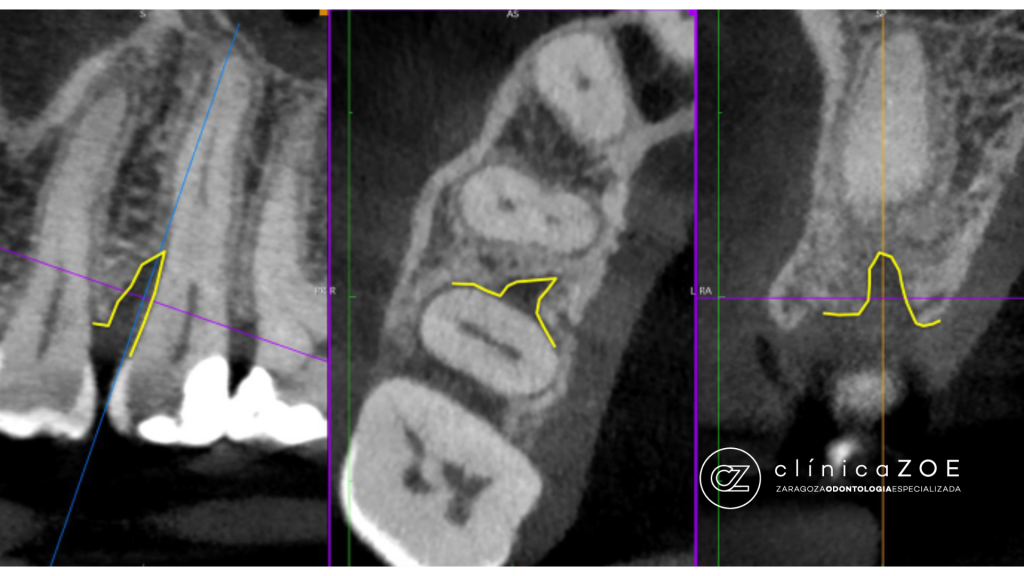

4. Radiología avanzada: combinamos proyecciones y, si es necesario, CBCT (TAC dental) para descartar fracturas radiculares o lesiones asociadas.

Hablamos de diente fisurado cuando el esmalte y/o la dentina presentan una grieta parcial que puede ser microscópica. No siempre se ve en radiografías y, muchas veces, no se aprecia a ojo desnudo; por eso su diagnóstico es un reto si no se cuenta con magnificación y luz coaxial de un microscopio clínico. Estas fisuras pueden desencadenar dolor al masticar o sensibilidad térmica y, si progresan hacia la pulpa (nervio) o la raíz, comprometer la viabilidad del diente.

3. Magnificación con microscopio: permite ver microgrietas invisibles, aplicar tinciones y valorar su trayecto.